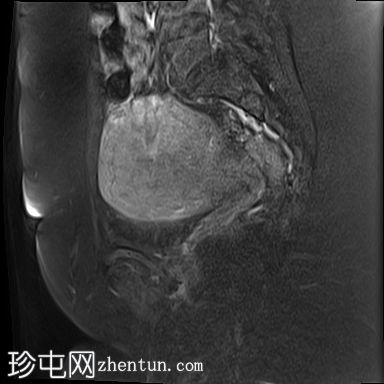

轴位

T2加权像

子宫前倾且体积增大,交界区呈边界不清、弥漫性对称性增厚。T2加权像和T2脂肪抑制像均显示条纹状高信号,无异常强化或扩散受限。

子宫内膜腔、交界区和外层肌层边界不清。

子宫肌层前壁可见一小而边界清晰的实性病灶,大小为1.1 × 1.0 cm。该病灶在T1加权像上呈中等信号强度,在T2加权像上呈低信号强度,无强化,无扩散受限。

MRI上,T2加权像上交界区增厚超过12 mm是子宫腺肌症的特征性表现。

本病例展示了弥漫性子宫腺肌症的典型MRI特征,包括交界区弥漫性增厚和T2加权像上呈条纹状高信号区域。